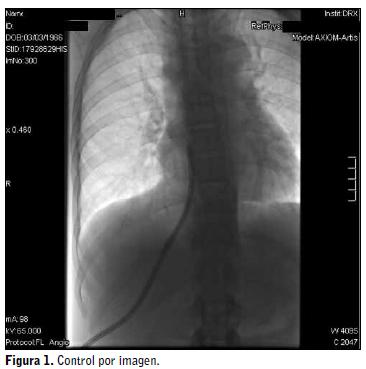

En las figuras 1 y 2 se muestra el acceso actual de la paciente: el catéter transhepático.

• Tras ello se le realizó un estudio endovascular que mostraba oclusión completa de vena iliaca izquierda y de cava inferior, lo que inhabilitaba los accesos femorales. En lo que respecta a los troncos superiores la situación no es mejor pues existe oclusión de venas subclavias, yugular derecha, tronco braquio-cefálico izquierdo y cava superior. Ante esta situación se colocó catéter permanente por abordaje transhepático a través de vena suprahepática derecha, con extremo en aurícula derecha9.

• El 17/01/2013 se le implantó nuevo catéter transhepático que fue recambiado el 20/03/2013 por disfunción. Este es su acceso actual y probablemente el único posible.